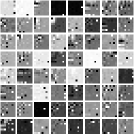

First, we study transform training based on Mayo Clinic data. As shown in Fig. 6, seven slices obtained at regular dose from three patients are used for transform learning. The number of pixels . Similar to the phantom experiments, overlapping patches are extracted with a patch stride. The number of overall training patches is about . We set for ST, , , for MARS2, , , , , for MARS3, , , , , , , , , for MARS5, , , , , , , , , , , , , for MARS7. The iteration number in Algorithm 1. Fig. 7 illustrates the learned transforms obtained with Mayo Clinic data. Different from the XCAT phantom case, these transforms up to MARS5 display more complex features and structures. The rich features of the MARS models better sparsify the training images over layers compared to the single-layer model (ST).